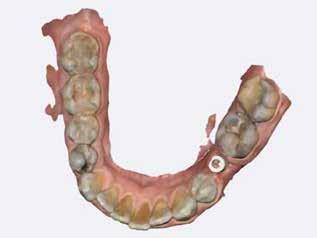

Egy 47 éves páciens jelentkezett nálunk egy alsó, hátsó foghiánnyal, ahol jelentős csontfelszívódást tapasztaltunk a moláris fogak korábbi eltávolítása miatt (1. ábra). Két implantátum körül is volt ínyrecesszió, illetve a keratinizált íny mennyisége minimális volt (kevesebb, mint 1 mm). 4 hónappal az implantációt követően ínykorrekciót végeztünk.

1. ábra: A műtét előtti szituáció, megfigyelhető az implantátumok közötti konkáv terület, ahova könnyen beragad az ételmaradék, és könnyen kialakul a periimplantitis.

A páciens mobilis implantátum körüli lágyszövettel rendelkezett, a keratinizált íny szélessége kevesebb volt, mint 1 mm és a nyálkahártya vastagsága nem érte el a 2 mm-t. Az ínyszél az implantátum platform vonalában volt. Az alábbi műtéti technikával jelentős javulást sikerült elérnünk az implantátum körüli lágyszövetek minőségében és a nem elmozduló keratinizált szövet szélesedett 4 mm-rel. A Kígyótechnikánál alkalmazott elforgatott lebeny a szabad keratinizált íny lebeny előnyeivel növeli a nem elmozduló nyálkahártya szélességét az implantátum körül. Biztosítja továbbá a jó vérellátást és a nyeles lebeny stabilitását, ami kisebb mértékű zsugorodást eredményez, mint egy szabad lágyszövet lebenyátültetésnél (29).